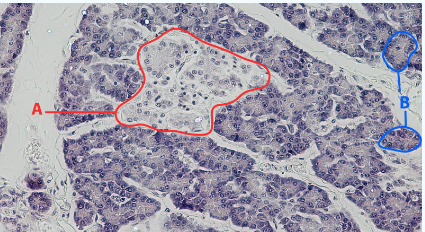

A

Islet

B

Acinar cells

Area

Pancreas